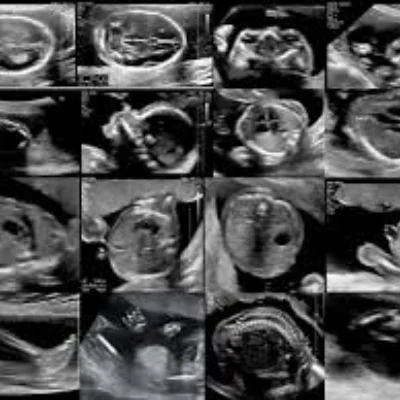

Obstetric Ultrasound

We specialize in obstetric imaging to support mothers and babies throughout pregnancy

Early Pregnancy Scans

Confirm gestational age and fetal viability

Fetal Growth Scans

Track development and detect anomalies

NT Scan

Nuchal translucency screening for chromosomal risks

Level II / TIFFA Scan

Detailed anomaly scan to assess fetal organs and structure

Our team ensures a calm, respectful environment for expectant mothers, with clear communication and compassionate care at every stage.